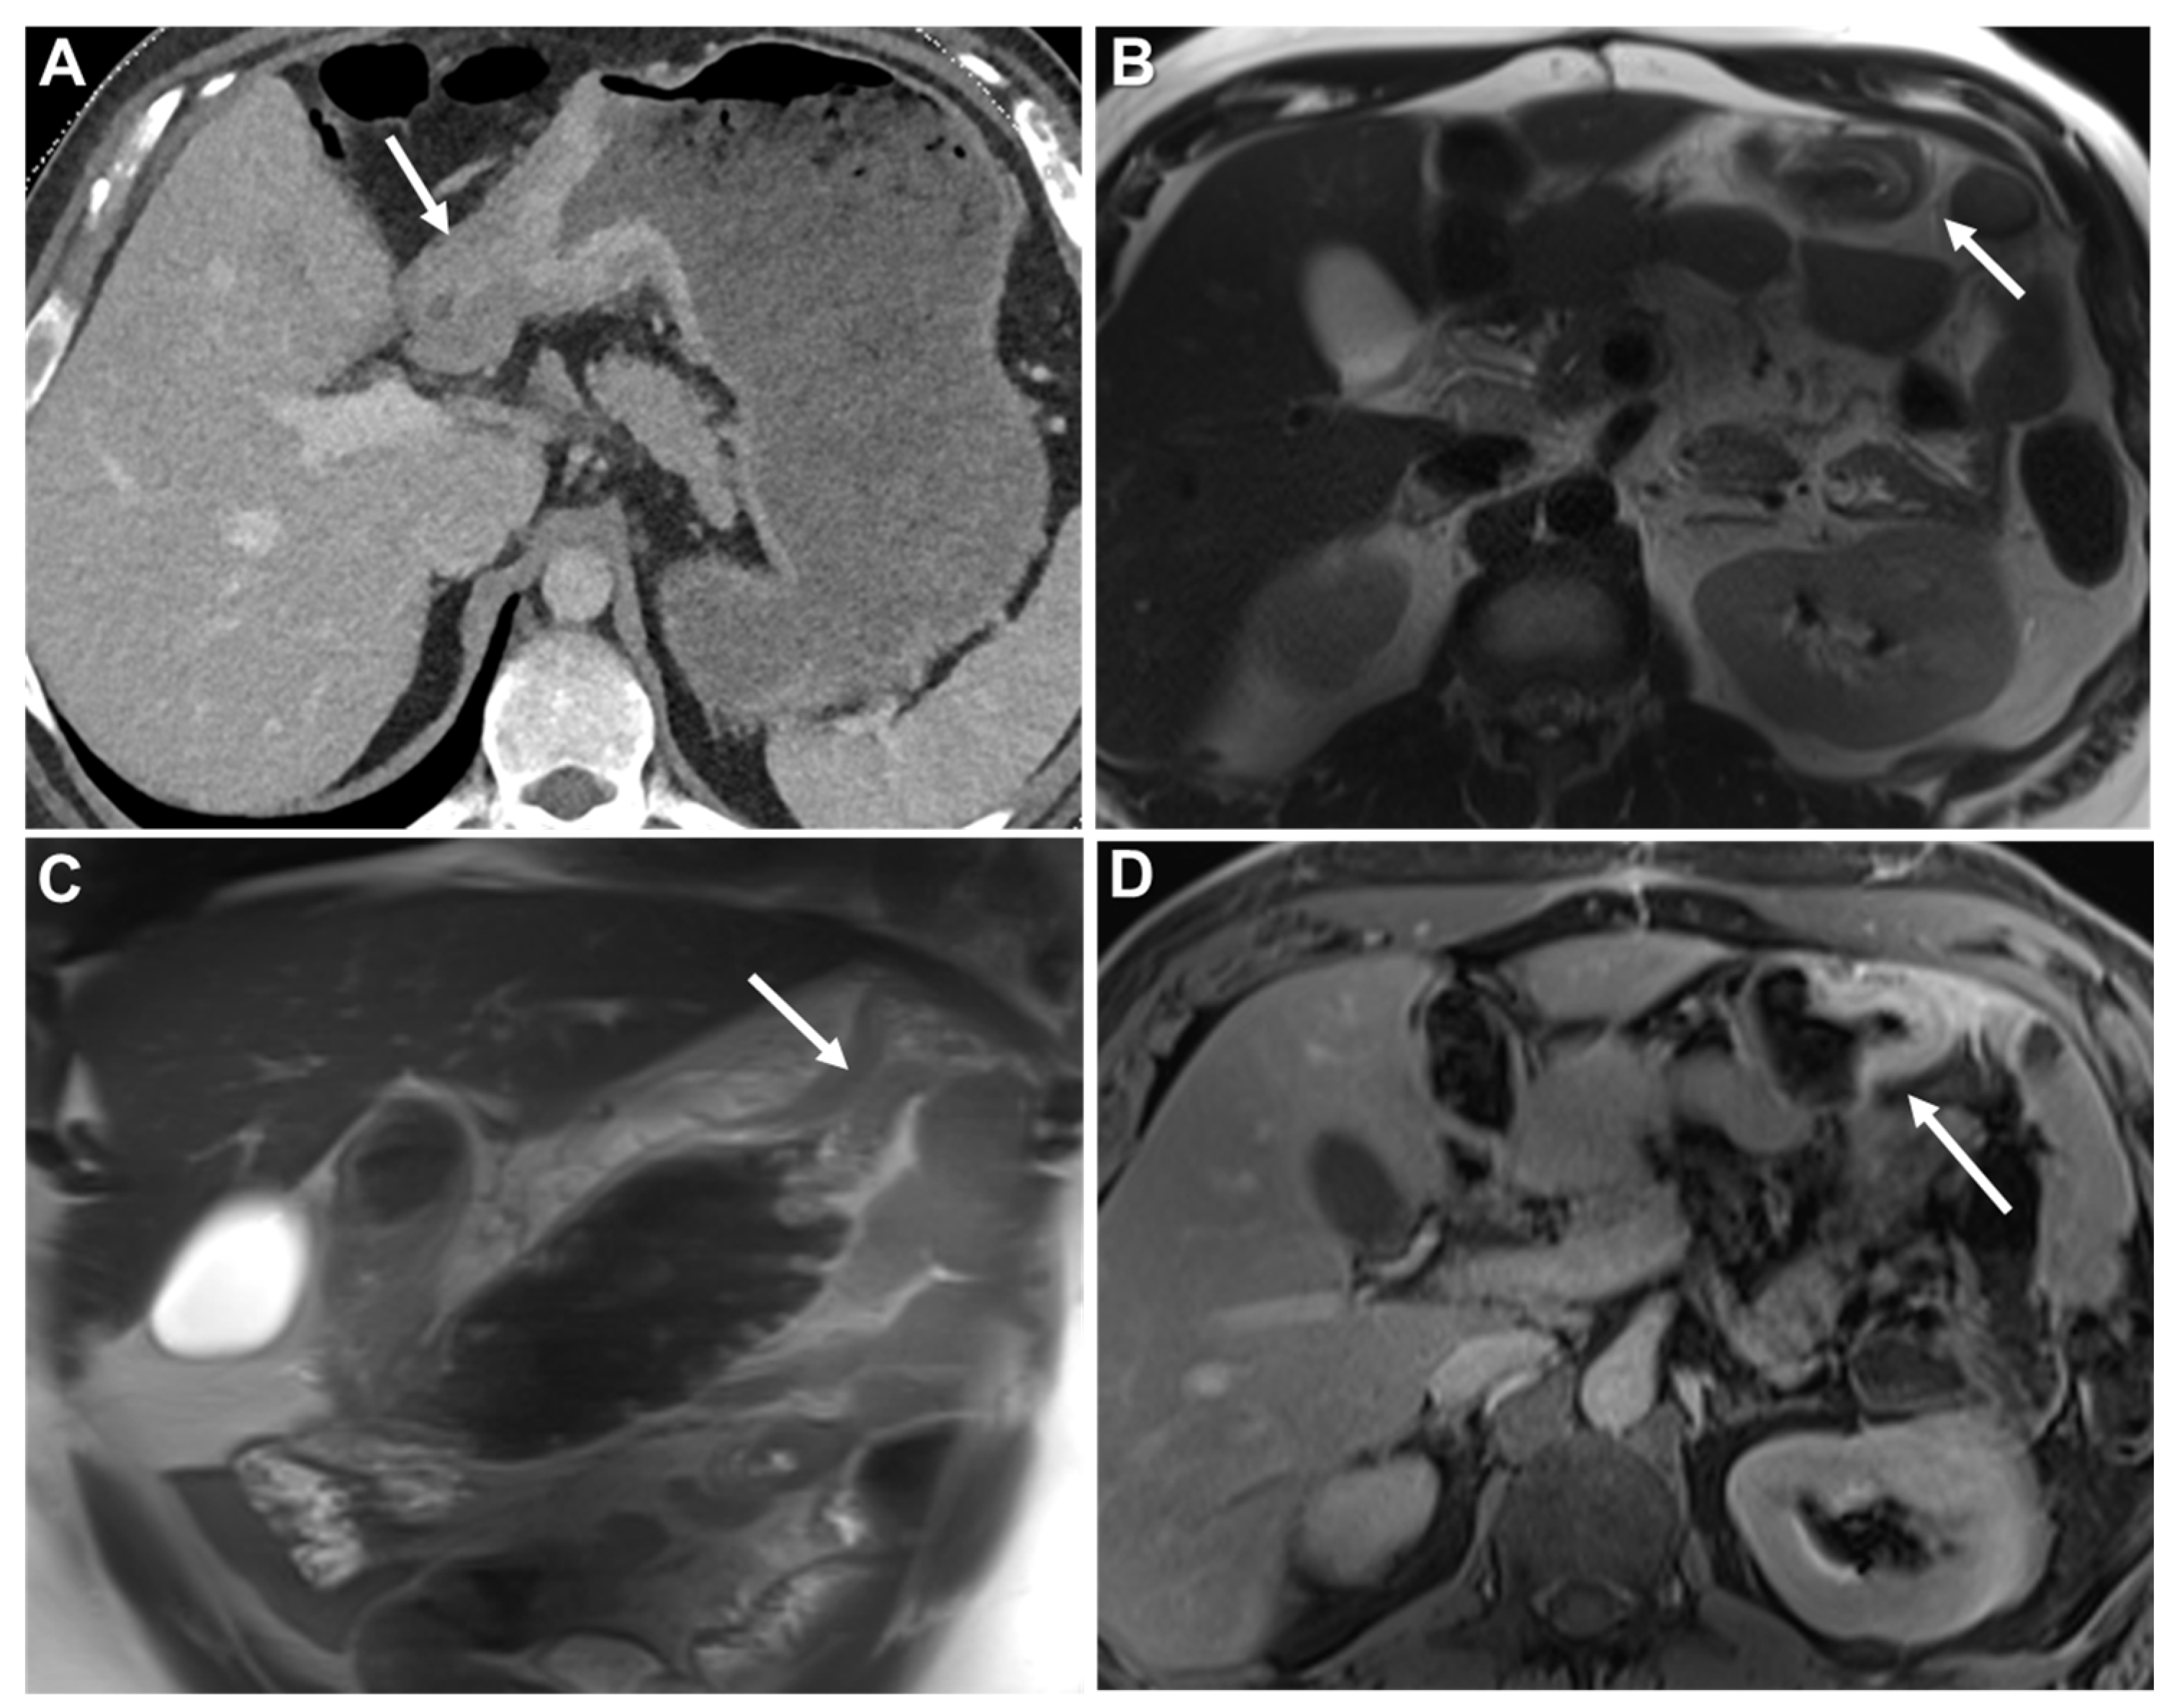

Homogeneous Delayed Enhancement